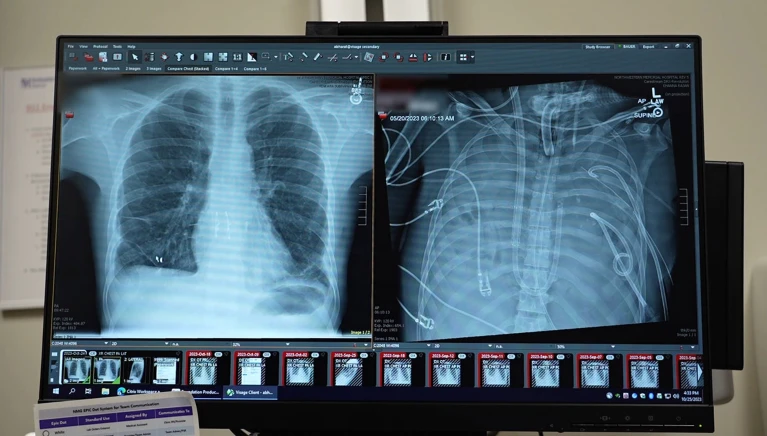

Un hombre de 33 años logró sobrevivir dos días completos sin pulmones gracias a un sistema de pulmón artificial externo desarrollado por un equipo médico de la Universidad Northwestern, en Estados Unidos.

El caso fue liderado por el cirujano torácico Ankit Bharat, de la Facultad de Medicina Feinberg, quien explicó que, a diferencia de otros dispositivos utilizados en situaciones extremas, este sistema mantiene un flujo sanguíneo continuo y equilibrado hacia el corazón, permitiendo que el órgano funcione con normalidad.

A pesar de estar conectado a ventilación mecánica, su estado se agravó al contraer una infección bacteriana resistente a los antibióticos, lo que derivó en shock séptico y el inicio de fallas cardíacas y renales. Ante la imposibilidad de realizar un trasplante inmediato, el equipo médico tomó una decisión inédita: extirpar ambos pulmones, principal foco de la infección.

Contra todo pronóstico, el paciente comenzó a mostrar una recuperación sorprendente. En menos de 48 horas, dejó de requerir medicamentos para mantener su presión arterial, su función renal se normalizó y su corazón volvió a operar con estabilidad. Una vez estabilizado, recibió un trasplante de doble pulmón, procedimiento que resultó exitoso. A casi tres años de la intervención, no presenta signos de rechazo ni deterioro pulmonar.

El sistema de pulmón artificial fue desarrollado originalmente durante la pandemia de COVID-19, con el objetivo de asistir a pacientes críticos que no podían acceder de inmediato a un trasplante. Si bien existen tecnologías como la oxigenación por membrana extracorpórea (ECMO), estas mantienen los pulmones dentro del cuerpo. El nuevo sistema, en cambio, es una versión modificada que se conecta directamente al corazón, permitiendo prescindir temporalmente de los pulmones sin comprometer la circulación.